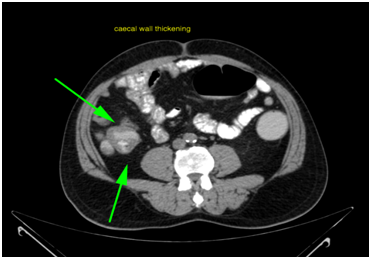

Cancer Caecum is not an un common disease. The symptoms are non specific except Anaemia, thus it is ignored. Any patient with appendicular mass or having persistent drain after Appendectomy cancer of caecum should be suspected. Out of all colorectal cancers cancer caecum is second common cause after sigmoid colon and Rectal carcinoma. Due to the location the symptoms differ as compared with other colon malignancy (Figures 1-3).

Figure 1 Caecal wall thickening.